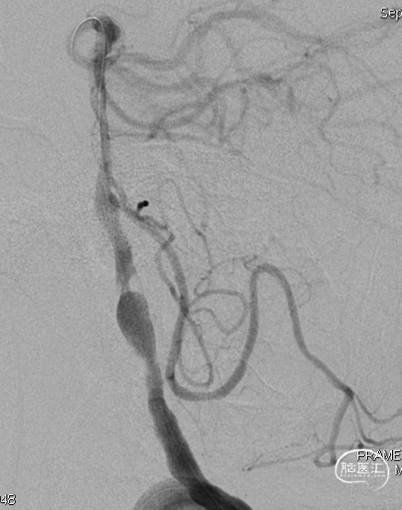

DSA示双侧椎动脉V4段狭窄,右侧为著且合并梭形动脉瘤。

术前DSA。